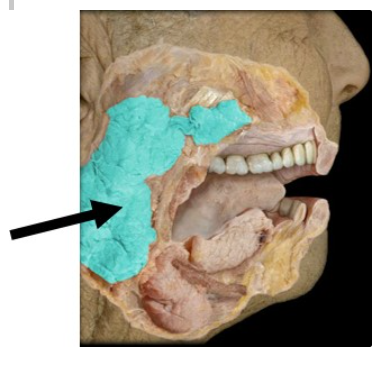

What gland is indicated in the figure?

Parotid gland

The structure indicated in the image secretes a watery solution containing an enzyme that breaks down __________ in response to __________ stimulation.

carbohydrates; parasympathetic